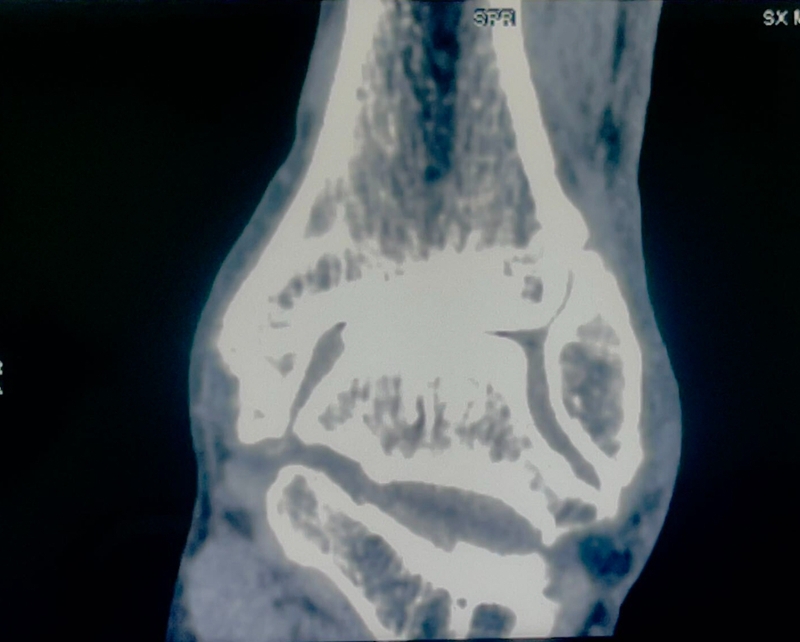

病例报告之二,xx,男,56岁,左踝创伤性关节炎。左踝崴伤6年,疼痛加剧3年。切口显露同前。

手术前资料